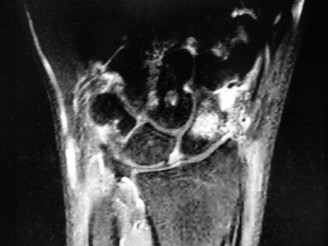

The correct answer is (E). The x-ray reveals a fracture of the scaphoid with sclerosis of the proximal fragment. This should raise suspicion of avascular

necrosis. MRI with contrast is the best method to determine the vascular status of the scaphoid.

A contrast MRI is obtained and is as shown below. What is the next course of action?

The correct answer is (C). The MRI (Fig. 3–4) reveals avascularity of the proximal pole. This is best treated by open reduction and internal fixation with a vascularized bone graft.

Figure 3–4(©) Sunil Thirkannad and Christine M. Kleinert.